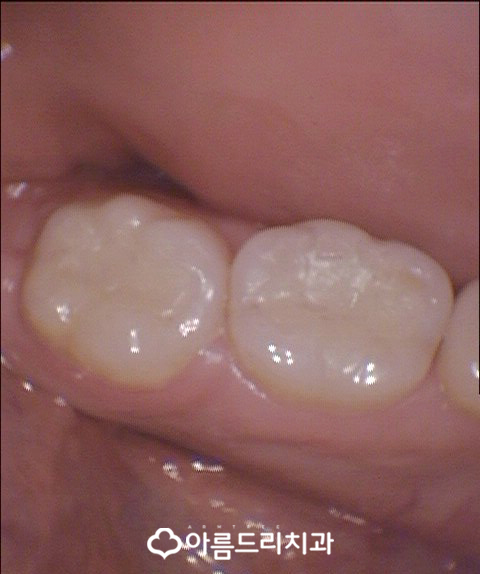

위의 사진은 치과치료에 대해 궁금해하시는 분들을 위하여 보다 자세히 구강의 모습을 보실 수 있도록 아름드리치과에서 사용하고 구강카메라를 통해 촬영한 사진이랍니다.

은색으로 치아의 윗부분과 옆부분 있는 것이 아말감이라고 하는 충치치료 수복재료인데요.

아말감 주변을 보시면 검은색으로 비쳐보이는 부분을 군데군데 확인해 보실 수 있을꺼에요. 또한 빨간색으로 표시한 치아의 옆쪽 부위는 이미 충치가 진행되어 구멍이 뻥 뚤린 상태!